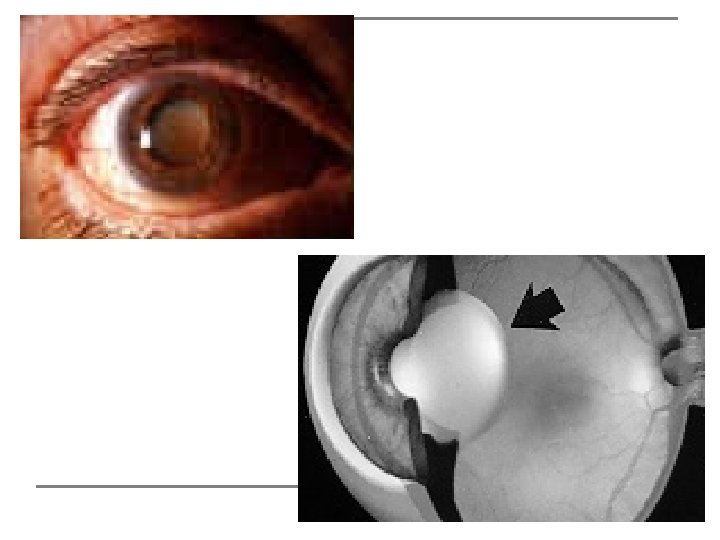

Catarata Consiste na opacidade parcial ou total do cristalino ou de sua cápsula. Pode ser desencadeada por vários fatores, como traumatismo, idade, Diabetes, uso de medicamentos, etc. . Apresenta-se como embaçamento visual progressivo. É uma doença conhecida há milhares de anos e sua cirurgia já é realizada há séculos. Atualmente, a técnica cirúrgica mais moderna para o tratamento da catarata, consiste da remoção do cristalino por microfragmentação e aspiração do núcleo, num processo chamado Faco-emulsificação, e posterior implante de uma lente intra-ocular.